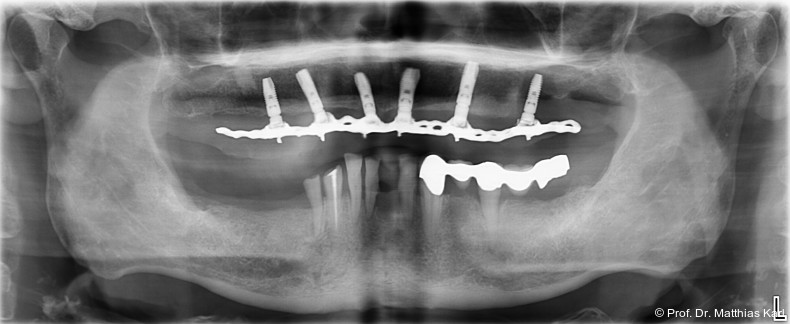

Die Insertion von zwei zahnärztlichen Implantaten zur Verankerung einer abnehmbaren Deckprothese stellt eine kosteneffektive Therapie dar, welche die Kaufunktion verbessert und zu hoher Patientenzufriedenheit führt, weshalb diese Versorgung in mehreren Ländern als „standard of care“ angesehen wird.1, 6, 14 Die dabei genutzten Verankerungselemente, welche die Prothese mit den Implantaten abnehmbar verbinden, sind entscheidend für den Prothesenhalt, die Patientenzufriedenheit und den klinischen Erfolg.14 Stege, Kugelkopf­anker und Locatoren werden hierfür häufig genutzt und führen zu einer Verbesserung der mundbezogenen Lebensqualität.4–6, 14 Die in Deutschland weitverbreiteten Doppelkronensysteme konterkarieren aufgrund der hohen Herstellungskosten die Grundidee einer kosteneffektiven Grundversorgung.8, 10, 15

Pfeilerdisparallelitäten und Transferfehler verhindern derzeit, dass neben den guten Überlebensraten implantatgetragener abnehmbarer Deckprothesen auch hohe Erfolgsraten unter Nutzung vorgefertigter Verankerungselemente erzielt werden. Ebenso stellt die Einstellung vorhersagbarer Retentionswerte ein klinisches Problem dar, da diese bei mehreren und zudem nicht parallelen Implantaten lediglich durch Ausprobieren erarbeitet werden kann. Aufgrund der geringeren Bauhöhe und ihrer Rotationssymmetrie sind Kugelkopfanker vorteilhafter und könnten durch Weiterentwicklung zum Ausgleich von Implantatdivergenzen die genannten Probleme lösen.